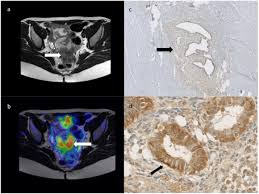

The Radiology Assistant Endometriosis Mri Detection from radiologyassistant.nl B, ct scan shows a nonspecific mass involving the right rectus muscle (arrow) subsequently proven to be endometriosis. After taking your medical and symptom history, and after performing a pelvic exam, your provider may recommend imaging. A ct or mri may show the endometriosis. Unusual sites of implantation and associated complications may make. Ct, endometriosis, female pelvis, mri, ultrasound. Endometriosis is a painful condition in which tissue that normally lines your uterus (endometrial tissue) grows in other parts of your pelvis, such as your ovaries or fallopian tubes. It can get worse before and during your period. An ultrasound, a ct scan, or an mri can make detailed pictures of your organs.

Fdg Pet Value In Deep Endometriosis Gynecological Surgery Full Text from media.springernature.com This type of endometriosis is called, deeply infiltrating or deeply infiltrative endometriosis die because it is found deep within the tissue or organ. It may vary from microscopic endometriotic implants to large cysts (endometriomas). After taking your medical and symptom history, and after performing a pelvic exam, your provider may recommend imaging. Although the ovary is the most common site of involvement, endometriotic implants may occur in other locations outside the pelvis. Endometriosis is a painful condition in which tissue that normally lines your uterus (endometrial tissue) grows in other parts of your pelvis, such as your ovaries or fallopian tubes. Endometriosis is a condition in which the type of tissue that forms the lining of the uterus (the endometrium) is found outside the uterus. Learn about treatment, causes, stages, surgery, and diagnosis. An ultrasound, a ct scan, or an mri can make detailed pictures of your organs.